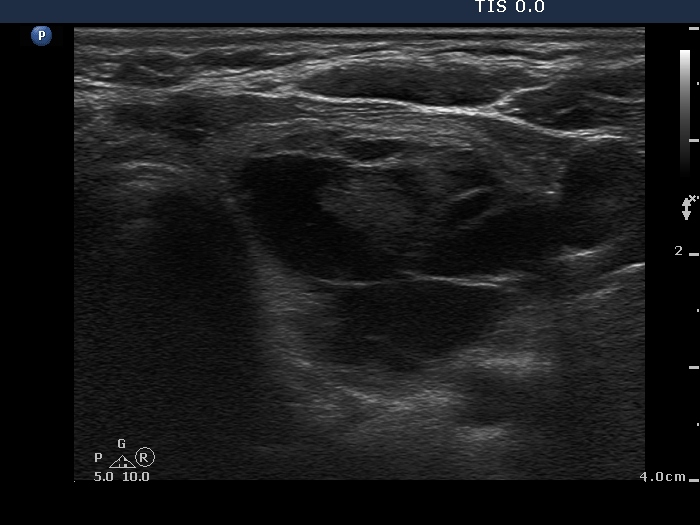

Benign cystic degeneration (cytological diagnosis) - case 662

The bright figures marked with arrows at the border of the cystic and solid part (right side of the nodule in the right image) can be easily misinterpreted as punctate echogenic foci (microcalcifications); these are posterior back wall enhancements caused by the microcystic area ventral to them.

There are comet-tail artifacts within the cystic fluid with a broader than usual tail.